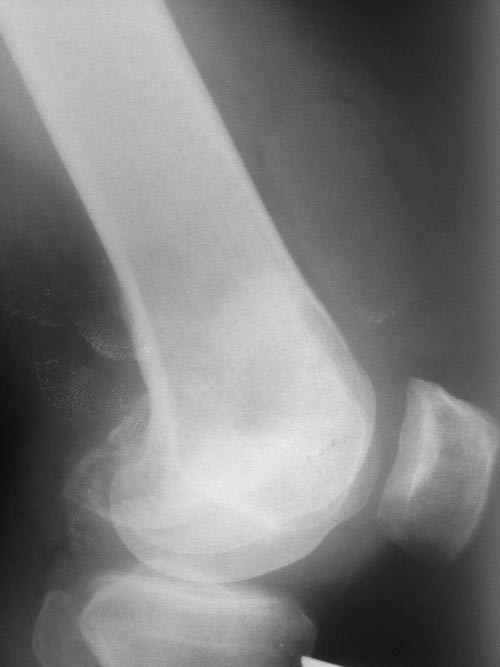

Пациент 37 лет. Около полугода беспокоила боль и припухлость в области коленного сустава. Не обследовался. неделю назад оступился и почувствовал резкую боль в коленном суставе. В настоящий момент находится в одной из больниц на скелетном вытяжении. Кт сделали, выложу позже (отмечается довольно большой дефект наружного мыщелка. Полностью обследован, первичный очаг не обнаружен.

Рентгеновский снимок

Уважаемый коллега! Видимо, это гигантоклеточная опухоль,которая протекала с не выраженной клинической симптоматикой, пока не произошел патологический перелом.Я бы попытался сохранить сустав. Сделать КТ оценить взаимоотношение отломков.

В возрасте между 20-40 годами из доброкачественных опухолей встречаются гигантоклеточные и энхондромы, а из злокачественных - только хондросаркома! Интенсивность и характер боли также имеет значение, например, усиление боли означает быстро растущую остеобластому, ГКТ или малигнизацию. Стрессовые и патологические переломы могут встречаться при злокачественном и при доброкачественном опухолях. Разрыв или вовлечение кортикального слоя означает метастазирование или стрессовый перелом. Четкие контуры показывает неагрессивную форму.

На основании этих данных можно предположить, что здесь имеем ГКТ дистального бедра. Первый случай, оперировать можно в обычном ортопедическом отделении. Доступ латеральный, удалить содержимое и заполнить цементом. Цитотоксичний эффект создается за счет температуры при твердении цемента. И опухоли с вовлечением в процесс более чем 40% нуждаются в дополнительной фиксации, иначе после удаления опухоли может пострадать стабильность. Любая латеральная пластина подойдет для этой цели.

Второй случай, коллапс латерального мыщелка за счет стрессового перелома. До операции надо уточнить диагноз биопсией и определить границу поражения на КТ и МРТ. Здесь имеется вовлечение кортикального слоя и вряд ли дистракционный метод поможет восстановить контур мыщелка. Онкологический вариант замещения с удалением неплохой вариант, но агрессивный. Возраст молодой и при наличии костного банка можно было восстановить аллографтом. Сегодняшняя технология (3Д и КТ) позволяет подобрать идеальный размер целого мыщелка (аллографт).